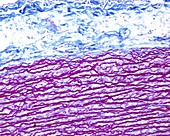

13416586 - Aorta tunica media and adventitia, light micrograph

12634941 - Aorta, tunica adventitia and media, LM

12634940 - Aorta, tunica adventitia and media, LM

12634939 - Aorta, tunica adventitia and media, LM